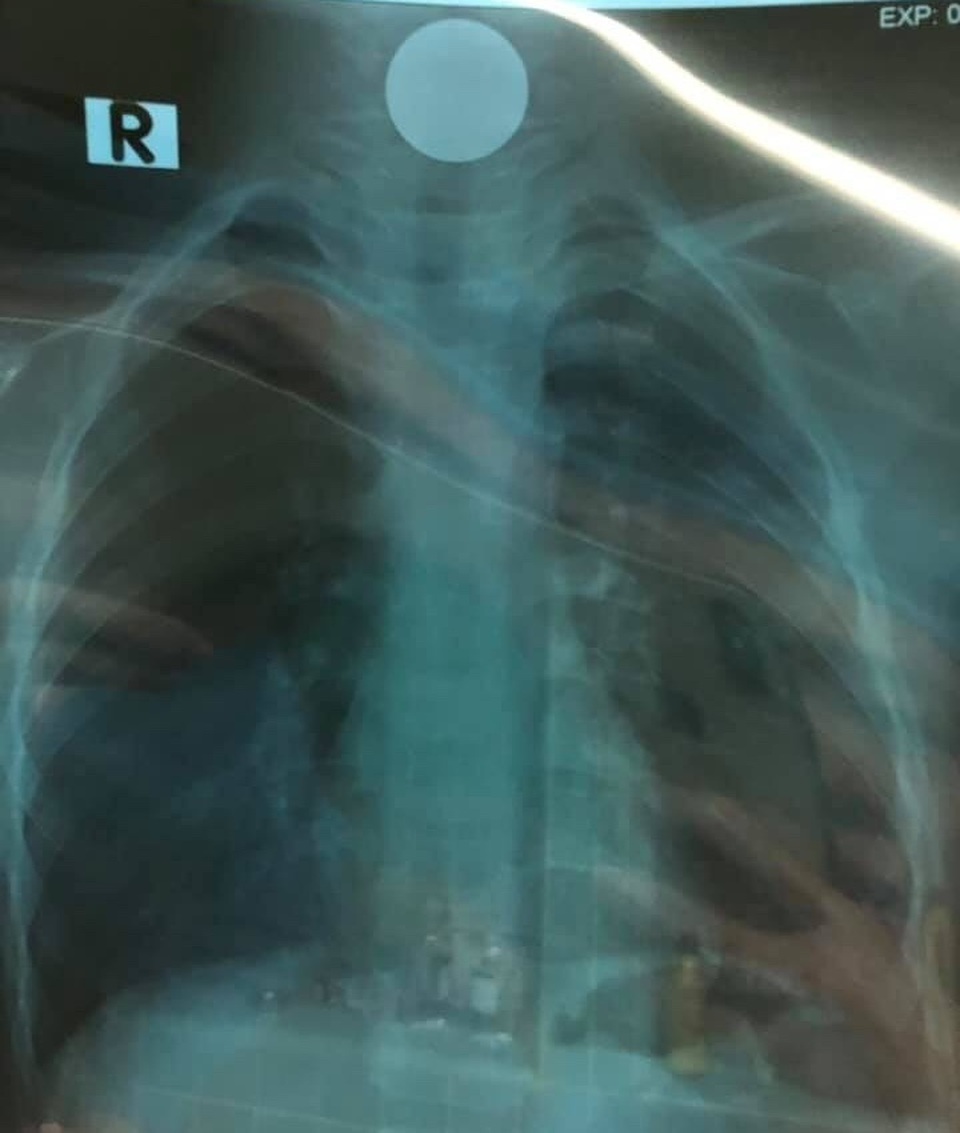

Đồng xu được lấy ra ngoài.